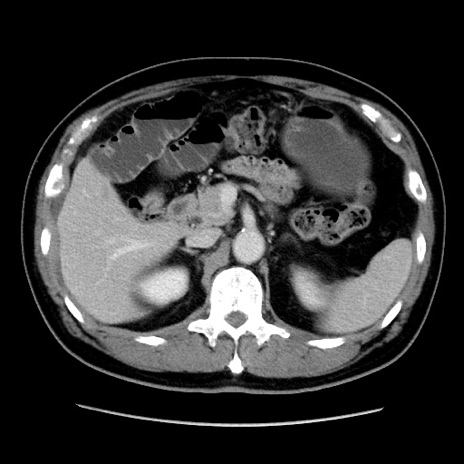

症例16(横断像)

【症例】 70歳代男性

【主訴】 腹痛、嘔吐

【現病歴】 約1ヶ月前より間欠的に腹痛と嘔吐あり、当院消化器内科を受診したところCTで多発する肝臓のLDAを指摘され、精査中であった。以降は消化器症状は安定していたが、2日前より嘔気と腹痛があり、同日より排便・排ガスが消失した。改善認めず、 本日、救急外来を受診した。

【既往歴】 大腸ポリープ切除後。

【身体所見】意識清明・会話良好、BT 36.3℃、BP 127/80mmHg、 P 80bpm、腹部:膨満あり、平坦・軟、上腹部正中および下腹部正中に圧痛あり、反跳痛なし、筋性防御なし。

【データ】WBC 7200、CRP 0.77